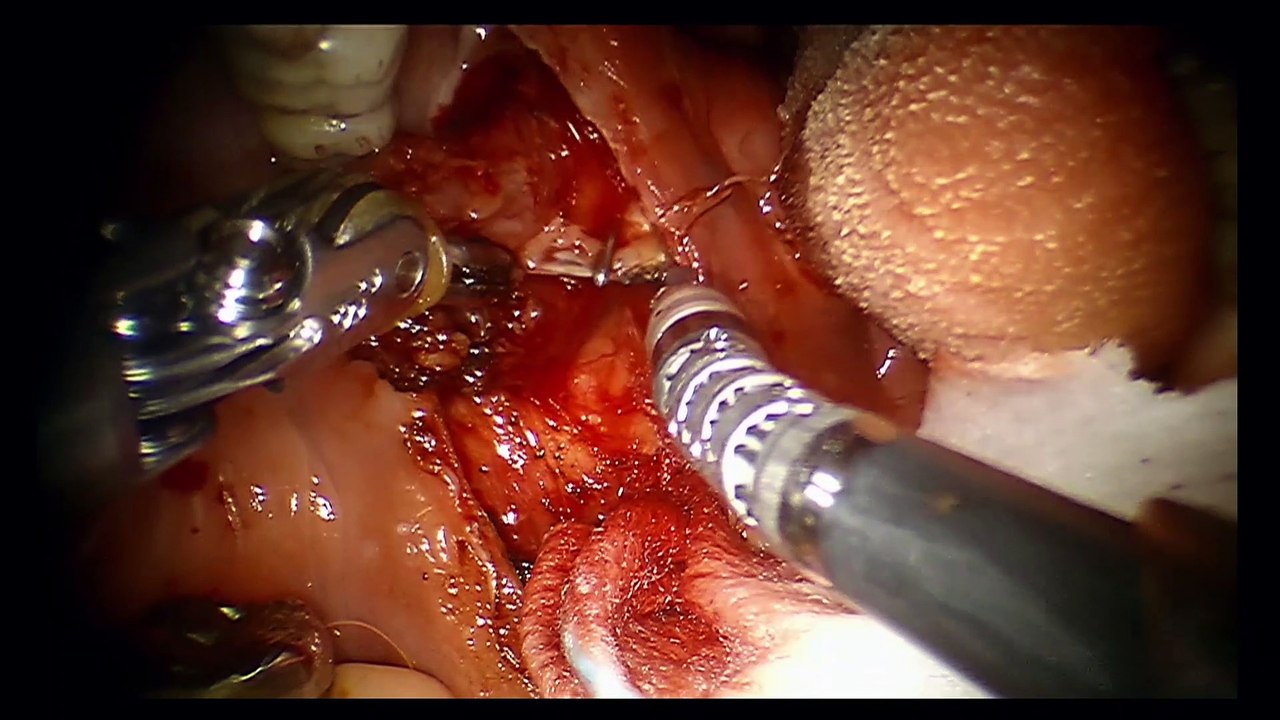

Chirurgies ganglionnaires des carcinomes épidermoïdes des VADS

Experts : Dr Agnès Dupret-Bories, Dr Jérôme Sarini, Dr Benjamin Vairel, Pr Sébastien Vergez

Technique du ganglion sentinelle: Etat de l'Art et perspectives